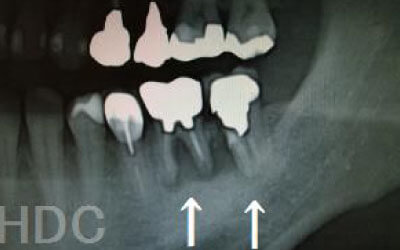

CTを使うことで、骨や歯の状態を3Dで確認でき、正確な距離測定も行えます。

骨の厚さや傾き、神経の位置などを事前にしっかりと計測することで、安全にインプラント治療を行うことができます。

骨が薄い場合、そのままインプラントを行うのはお勧めできません。

ただし、事前に骨を増やす治療を行ったり、インプラントと同時に骨を増やす治療を施したりすることで、インプラントは可能です。

1)インプラント治療を行う前に、骨の治療が必要かもしれません。

2)骨の治療から始めると、その分、治療期間が長くなります。

3)骨の治療は、通常のインプラント治療よりも難易度が高いため、経験の豊富な先生やインプラント認定医のいる歯科医院で治療を受けることをお勧めします。

4)骨の状況をしっかり把握するためにも、CT撮影が必須となります。